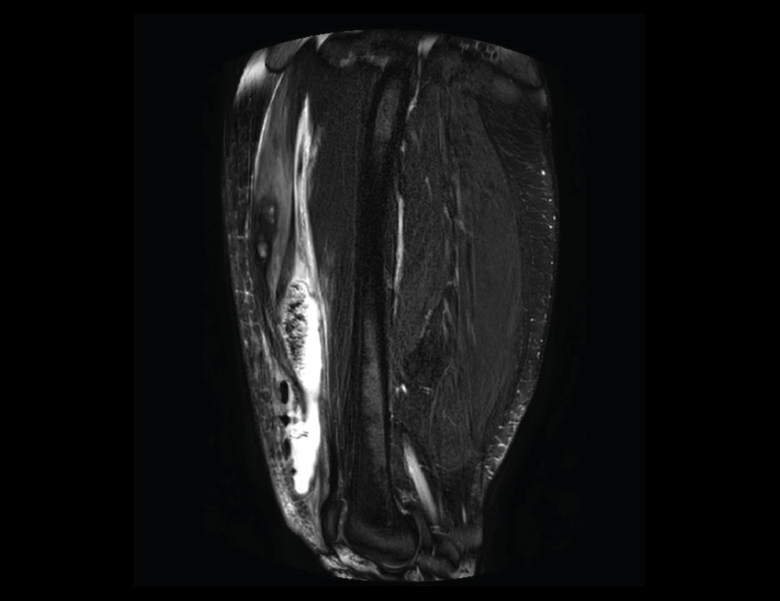

Figura 52. A: corte de secuencia coronal T2 Fat-Sat con infartos óseos en el fémur y la tibia; B: corte de secuencia sagital T1 con infartos óseos en el fémur y la tibia.